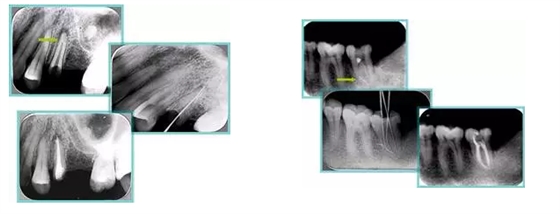

共有 4 張 X 線片,分別是術(shù)前、診斷絲 、主牙膠尖確認(rèn)、術(shù)后。

( 1 )術(shù)前:術(shù)前 X 線片用來了解牙齒的大概情況。術(shù)前預(yù)期為多根牙時(shí) X 線片應(yīng)偏頭拍攝。

( 2 )診斷絲:根據(jù)術(shù)前 X 線片進(jìn)行開髓、根管的初步預(yù)備后,需要插入診斷絲,用來指示工作器械位置。常用 10 號或 15 號擴(kuò)大器作為診斷絲插入牙髓腔。

( 3 )主牙膠尖確認(rèn):通過術(shù)前預(yù)期和診斷絲診斷,明確工作長度、牙根走向,進(jìn)行根管預(yù)備。之后應(yīng)進(jìn)行主牙膠尖(中銼)確認(rèn),已明確根管是否適合充填。

( 4 )術(shù)后:觀察治療效果。